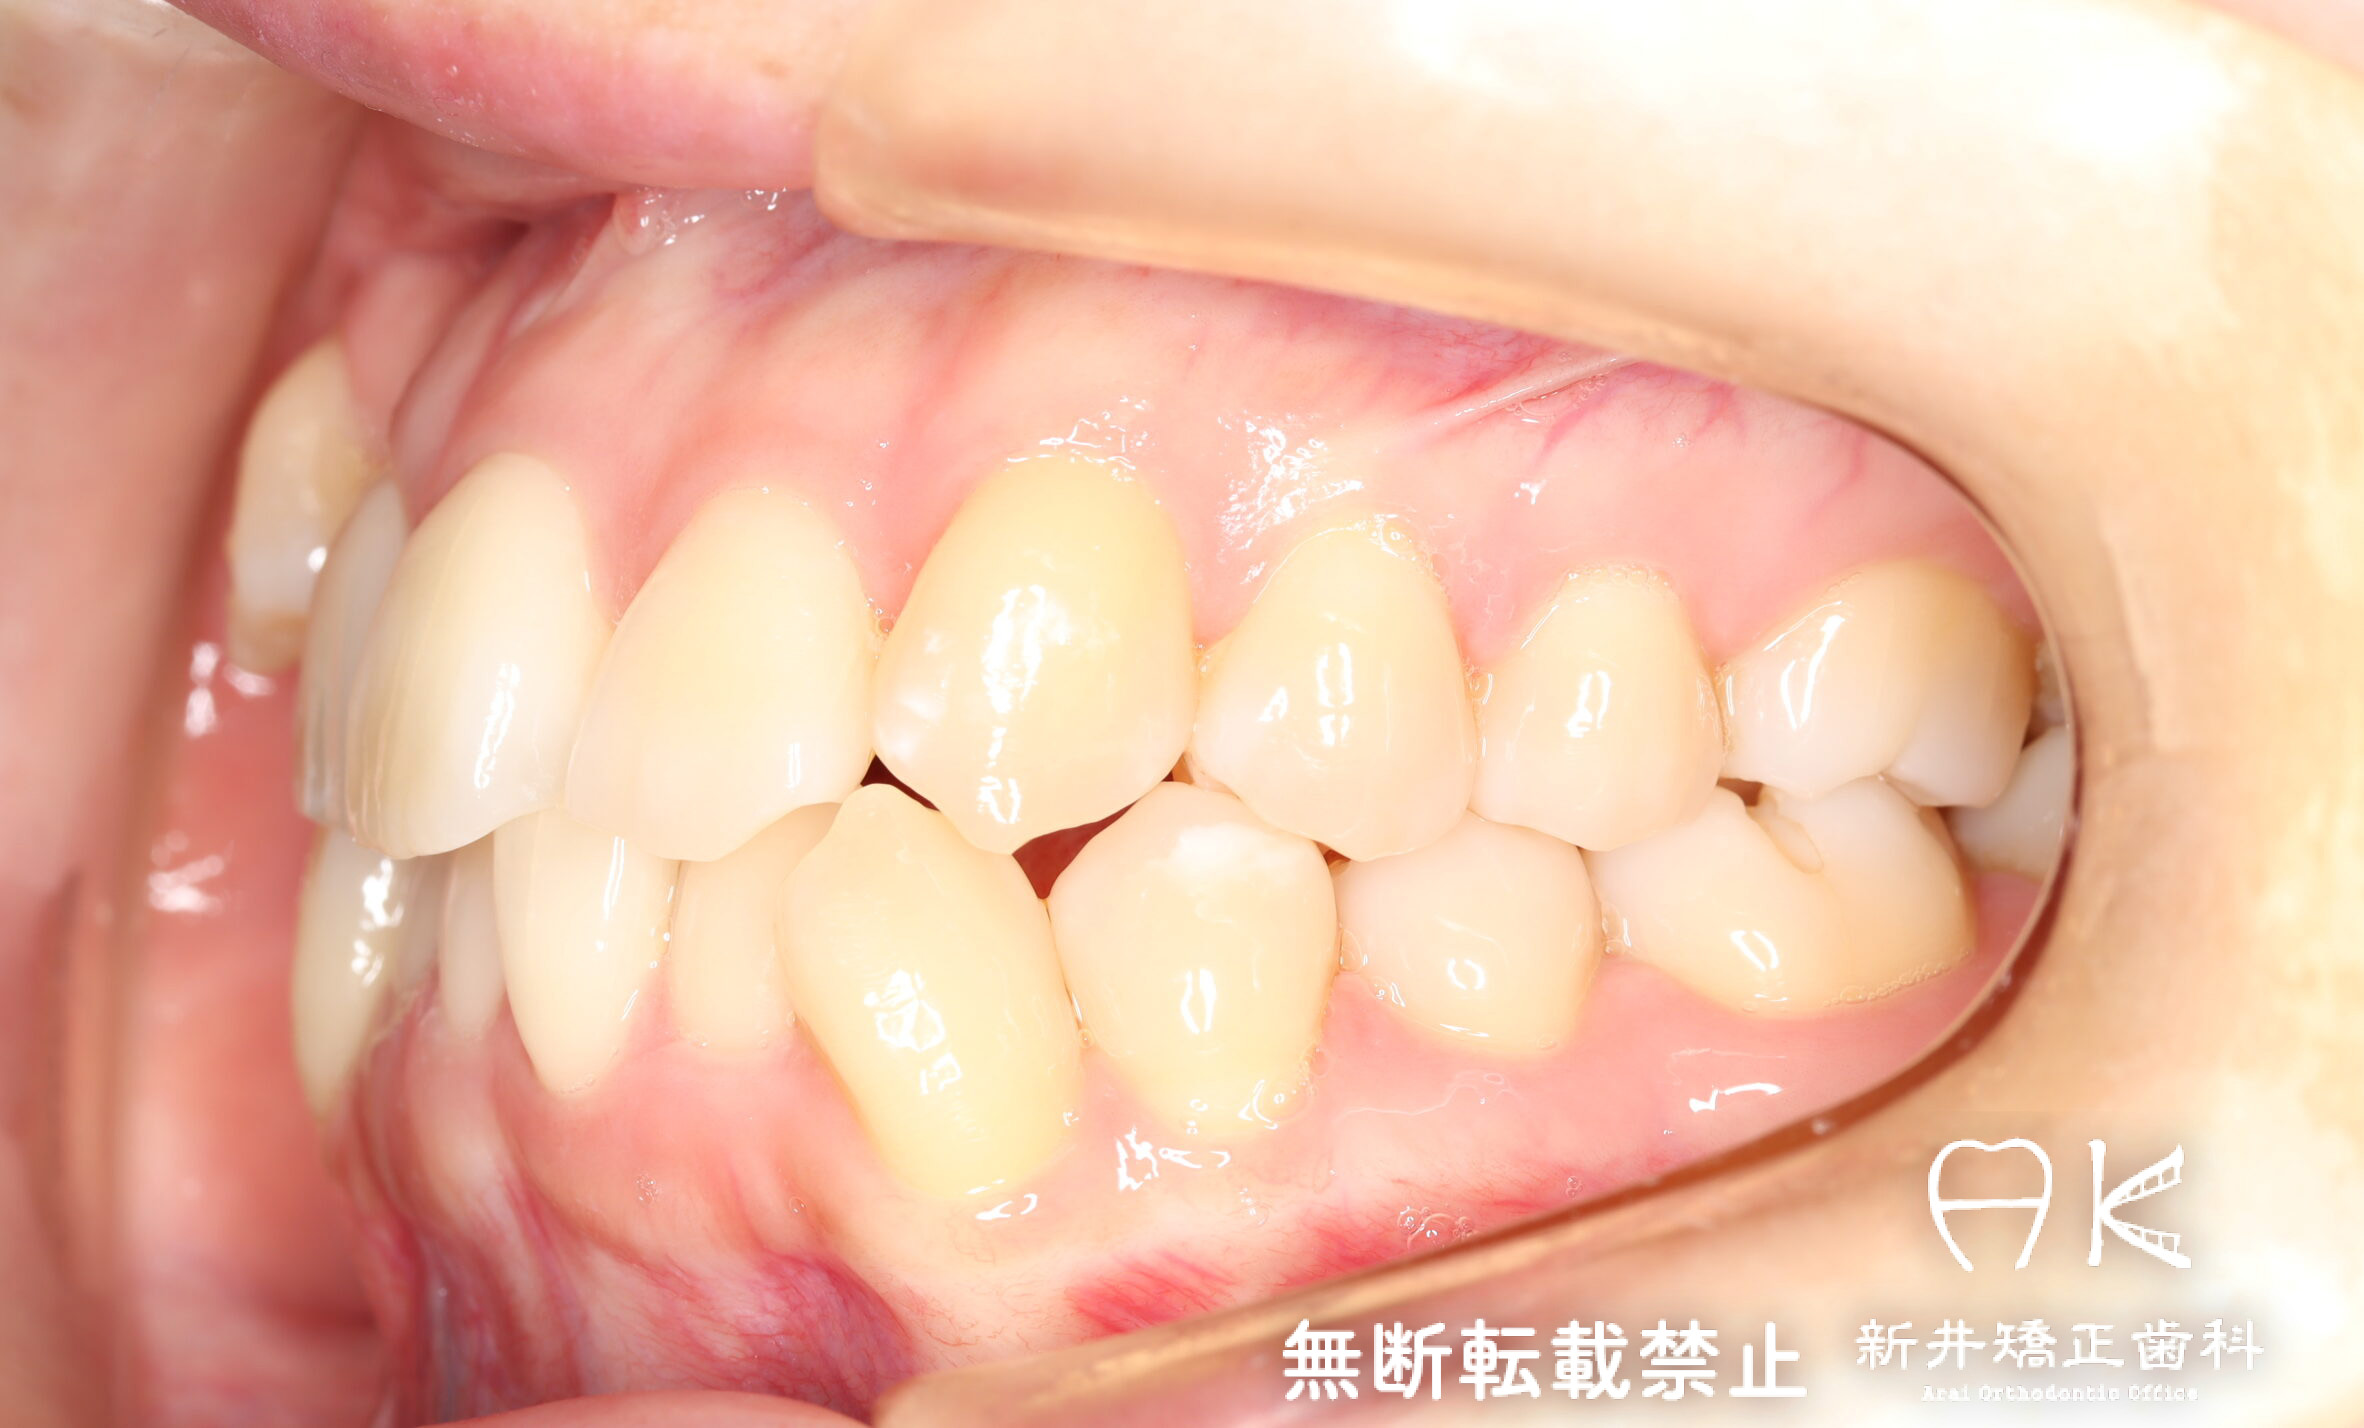

| 治療前 | 骨格的には受け口の患者さんですが、上顎前歯の唇側傾斜が大きく、患者さんとしては出っ歯だと思われていたパターンです。 元々口元の突出感はほとんどなかったため、歯を抜かずに上下顎ともに歯列を後方に移動させることにより主訴を改善させることとしました。 |

|---|---|